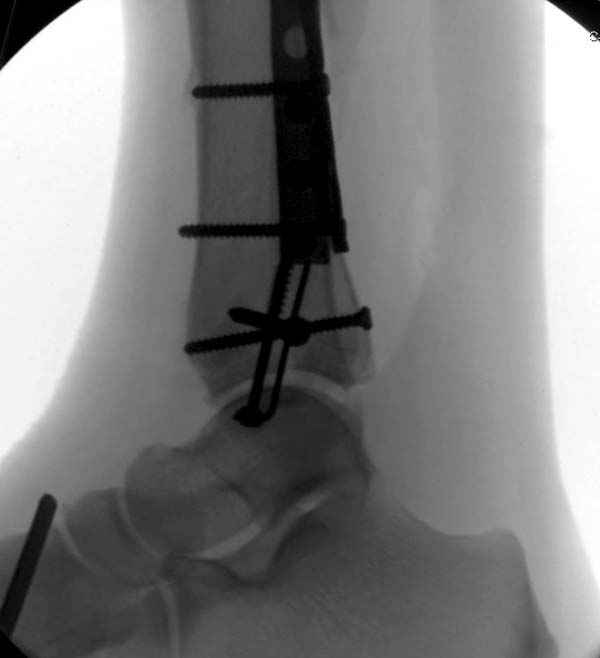

По снимкам довольно сохранный сустав, и такой сустав желательно попытаться восстановить всеми возможными мерами.

Артродез штифтом от Синтеза - немного агрессивно, а для улучшения качества жизни вместо артродеза голеностопа можно было бы предложить артродез подтаранного сустава. Тремя 6.5 мм каннюлированными шурупами через пятку.

Насчет пилона, прошло достаточное время для консолидации и прекрасная возможность для демонстрации, что такие случаи могут быть успешно вылечены остеотомией, несмотря на засторелость.

Из заднего доступа остеотомия тонким остеотомом и коррекции на ЭОПе.

Без применения сложной конструкции, а обычными параллельными шурупами. Шурупы в 3.5 мм и дополнительно фиксация крючковидной пластиной, сделанной из 3.5 mm semitubular пластиной, Butress или аntiglade фиксация.